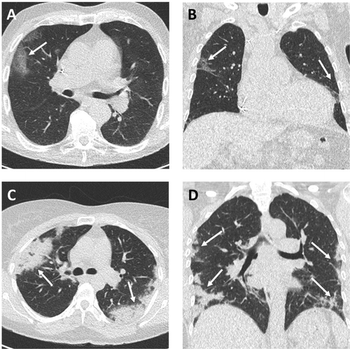

Research reveals lung findings not typically associated with viral pneumonia.

Radiologists must continue to be aware that patients obtaining scans for non-respiratory symptoms could still present findings of COVID-19.